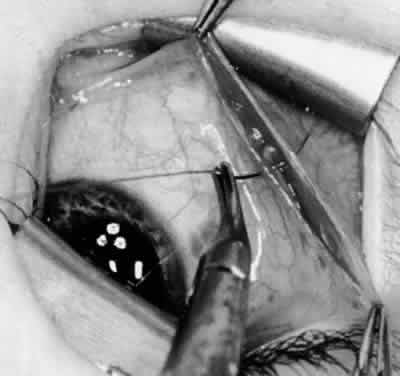

Fig. 5. The Stevens hook is placed adjacent to the posterior edge of the inferior oblique muscle and rotated as the inferior oblique muscle is drawn into the operative field. A forceps is used to retract the redundant Tenon's capsule, encapsulated fat, and intermuscular septum as the muscle is drawn further into the operative field with the Stevens muscle hook.

Fig. 6. The Westcott scissor is used to open the intermuscular septum along the posterior border of the inferior oblique muscle. Care is taken to cut adjacent to the tip of the Stevens muscle hook. This incision is important because it helps to avoid damaging the Tenon's capsule and releasing fat, which leads to the adherence syndrome and postoperative hypotropia.